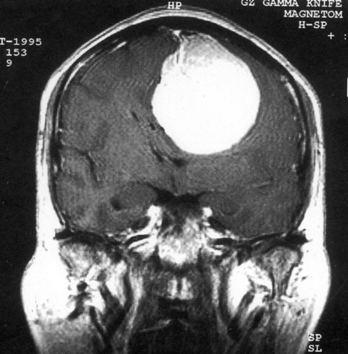

问题 病历摘要:??患者,男,40岁。发作性左下肢抽搐1年余,每次发作3~5分,每周发作1~2次。每次发作后感左下肢乏力,约半日后可自行恢复。既往身体健康。体检:神清,头顶部偏右有局限性骨性隆起(1.5×1.5cm),左鼻唇沟稍浅,伸舌居中。感觉、运动无明显异常。左浅反射减退,左下肢腱反射稍亢进,左Babinski征(-)。 可选择下列哪些检查帮助诊断